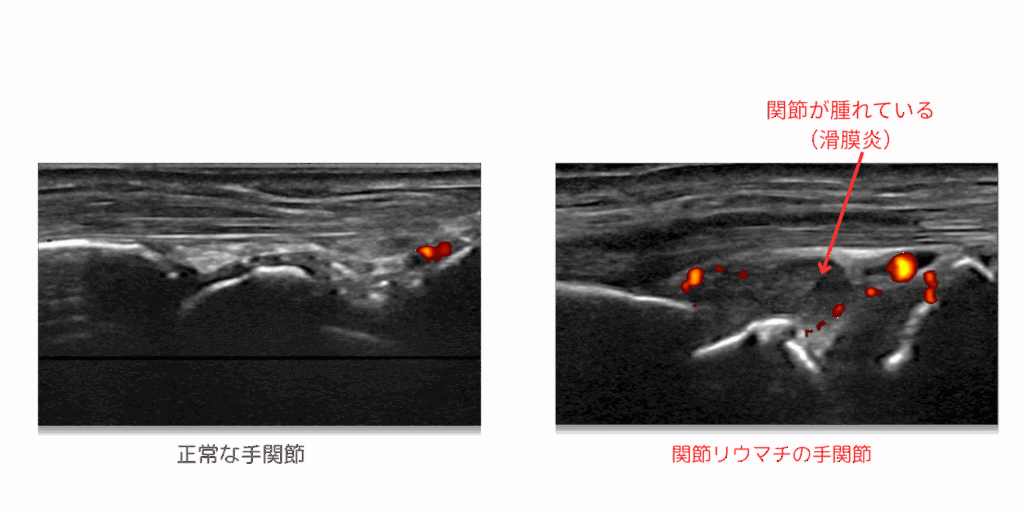

関節リウマチドック

関節リウマチは女性の100人に1人程度の割合で発症する病気とも言われています(男性にも発症する病気です)。発症は50歳代に多いとされますが、実際は若年者(20歳代)や高齢者(70歳以上)でも発症します。自己免疫の異常で関節(滑膜組織)に炎症を生じ、骨や軟骨が壊れていきます。一般的には “関節リウマチは手指に生じやすい” と思われていますが、そうではありません。手首・肩・肘・膝・足首・足趾などのあらゆる部位に発症するため、これらの関節の状態をエコーで評価することで、早期発見につなげることが可能です。

関節リウマチは男性にも生じる病気です。あなたの旦那さんやご兄弟は、関節の痛みをそのままにしていませんか?

| 検査の種類 | 検査内容 | ||

| 理学的検査 | 問診(既往歴・業務歴)、医師診察 | ||

| 血液検査 | RF、抗CCP抗体、MMP-3、CRP | ||

| 画像検査 | 手指手関節エコー(+気になる関節) |